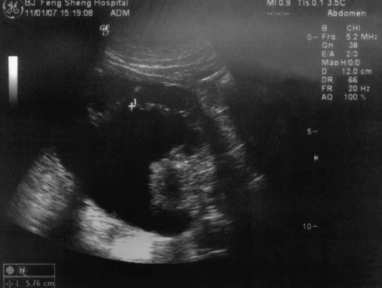

第123例附图1 输尿管癌

左肾盂明显扩张积水

第123例附图2 左肾实质厚度1.53cm;尚属正常(不薄),故肾积水为急性(近期积水)